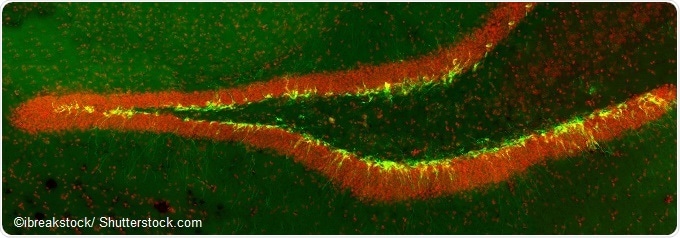

New born neurons in the transgenic mouse hippocampus (dentate gyrus) labeled with green fluorescent marker. Implicated in mood and memory.

The hippocampus is a brain region that converts experiences into long-term memories and plays a particularly important role in spatial memory, which helps a person remember information such as where they parked their car in a multi-storey car park or what they ate for breakfast.